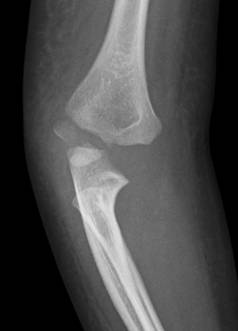

這題的關鍵在於辨識兒童肘部X光片上,遠端肱骨外側髁(capitellum)的骨折線與移位。4歲兒童的骨化中心發育程度是判讀的重要依據。

選項拆解